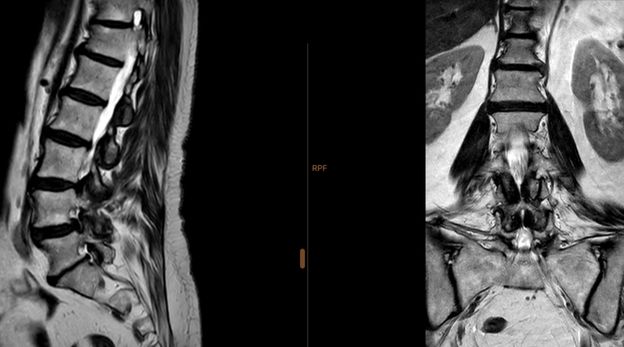

A ressonância magnética à coluna é um exame de imagem não invasivo e sem radiação que permite avaliar com elevada precisão as diferentes regiões da coluna vertebral: cervical, dorsal, lombar e lombo-sagrada. É frequentemente utilizada no diagnóstico de hérnias discais, compressões nervosas, alterações inflamatórias, traumáticas ou tumorais.

A ressonância magnética (RM) à coluna é um exame que recorre a campos magnéticos e ondas de radiofrequência para obter imagens detalhadas das estruturas da coluna vertebral. Permite observar com clareza os discos intervertebrais, a medula espinal, as raízes nervosas, as articulações e os tecidos moles circundantes.

A ressonância magnética da coluna lombar analisa os cinco segmentos inferiores da coluna lombar, que suportam grande parte do peso corporal. É frequentemente solicitada para investigar lombalgias, hérnias discais, compressões nervosas que causam dor ciática, estenose do canal lombar, alterações degenerativas, espondilolistese, lesões pós-traumáticas, etc.

O paciente é colocado deitado numa maca, com a coluna apoiada numa bobina adequada à região a estudar. A cabeça pode ser posicionada numa bobina específica no caso de RM à coluna cervical. São adquiridas imagens em vários planos, com cortes finos e alta resolução.